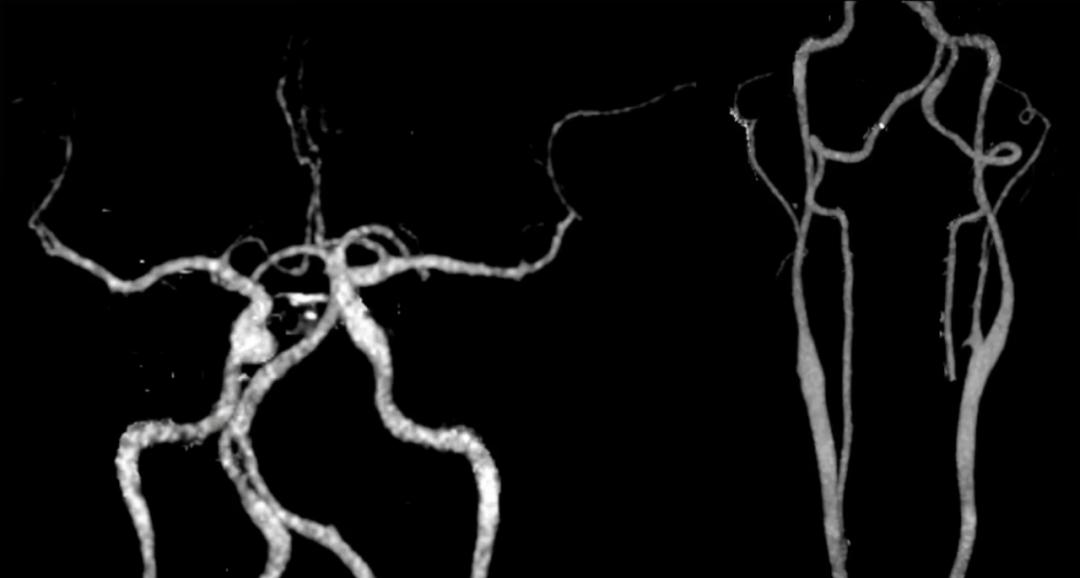

顺藤摸瓜,查了一下头颈CTA,未见大血管狭窄闭塞。

患者低血压、多发性梗死,却没有大血管闭塞。重新考虑病因,会不会是血栓栓塞(原因②)或者凝血异常(原因③)导致的呢?

经过检索,得到9篇文献,在所描述的11例类似CADASIL病例中,所有患者均无大动脉狭窄,且多与低血压及血容量降低有关。